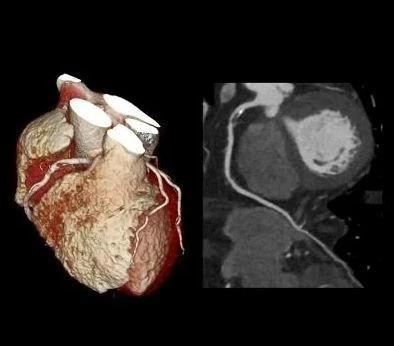

7_ga2Ud018svc4v4sqf3s63a7_f0tse7.jpeg?type=e1920_std

9_aa2Ud018svc1exa1rv8hrsu0_f0tse7.jpg?type=e1920_std

저렇게 슬라이스로 잘라서 한 장씩 보는 셈입니다.

단면들을 모아서 다시 3차원으로 만들 수도 있어요.

이런 식으로.. 다시 영상을 만들어서 입체적으로 구조를 다시 볼 수도 있습니다.